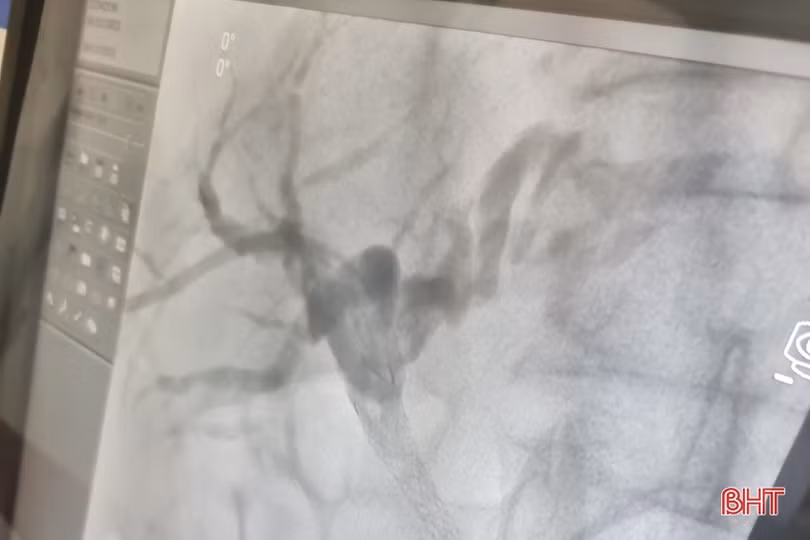

Các bác sỹ BVĐK tỉnh thực hiện thành công đặt stent đường mật dưới hệ thống chụp mạch số hóa xóa nền cho bệnh nhân.

Dưới sự hướng dẫn của các bác sỹ Bệnh viện Đại học Y Hà Nội, các bác sỹ BVĐK tỉnh đã thực hiện chụp đường mật xuyên gan qua da. Khi phát hiện chính xác vị trí hẹp đường mật, các bác sỹ đã tiến hành đặt một stent vào vị trí hẹp để ống mật được thông tắc, dịch mật được chảy xuống tá tràng.

Hình ảnh stent trong ống mật chủ sau đặt stent ống mật chủ cho thấy dịch mật lưu thông tốt qua ống mật chủ.